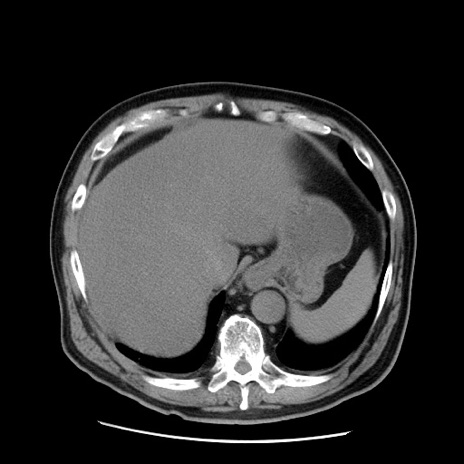

症例20(横断像)

【症例】 60歳代男性

【主訴】 腹部膨満、嘔吐

【現病歴】5日前頃より倦怠感を認め食事量減少し4日前の朝嘔吐、食事摂取困難となった。 3日前近医受診し点滴施行され整腸剤などを処方された。 当日他院を受診し、腹部膨満著明、炎症反応の上昇(CRP10.8、WBC11200)あり、紹介受診となる。

【身体所見】 意識JCS1 受け答えがはっきりしないBP 111/57mHg、 P 67bpm、、BT35.2°C、SpO2 97%(RA)、 腹部:膨隆、打診で鼓音あり、全体的に圧痛有り、腸蠕動音(-)、反跳痛ははっきりせず。

【データ】WBC 11400、CRP 14.20